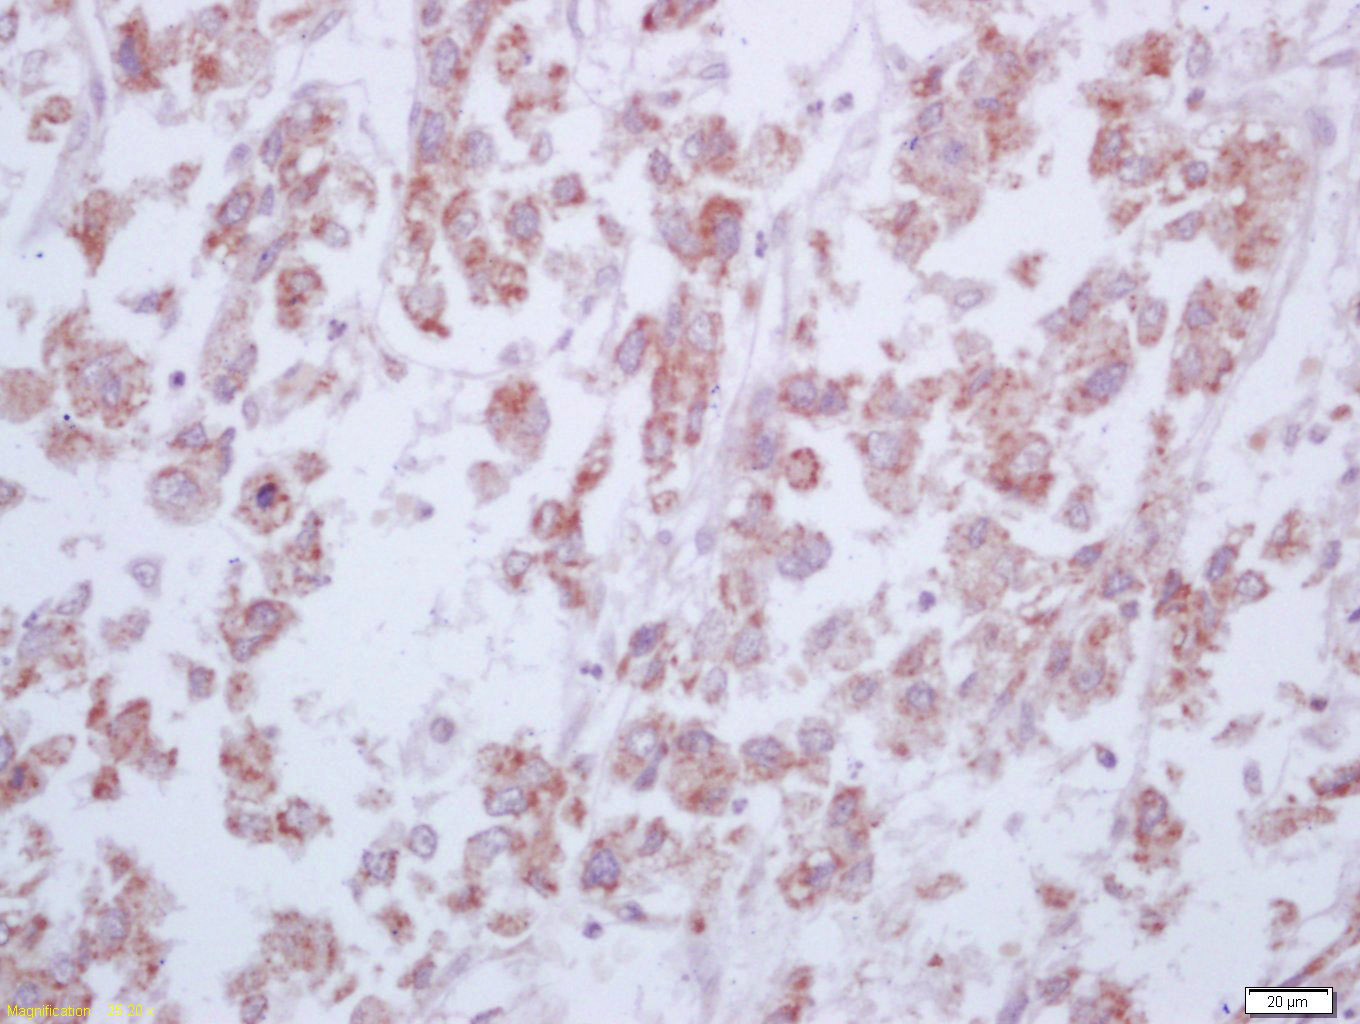

產(chǎn)品圖片

Tissue/cell: human liver carcinoma; 4% Paraformaldehyde-fixed and paraffin-embedded; Antigen retrieval: citrate buffer ( 0.01M, pH 6.0 ), Boiling bathing for 15min; Block endogenous peroxidase by 3% Hydrogen peroxide for 30min; Blocking buffer (normal goat serum,C-0005) at 37℃ for 20 min; Incubation: Anti-Arginase 1 Polyclonal Antibody, Unconjugated(bs-8585R) 1:200, overnight at 4°C, followed by conjugation to the secondary antibody(SP-0023) and DAB(C-0010) staining